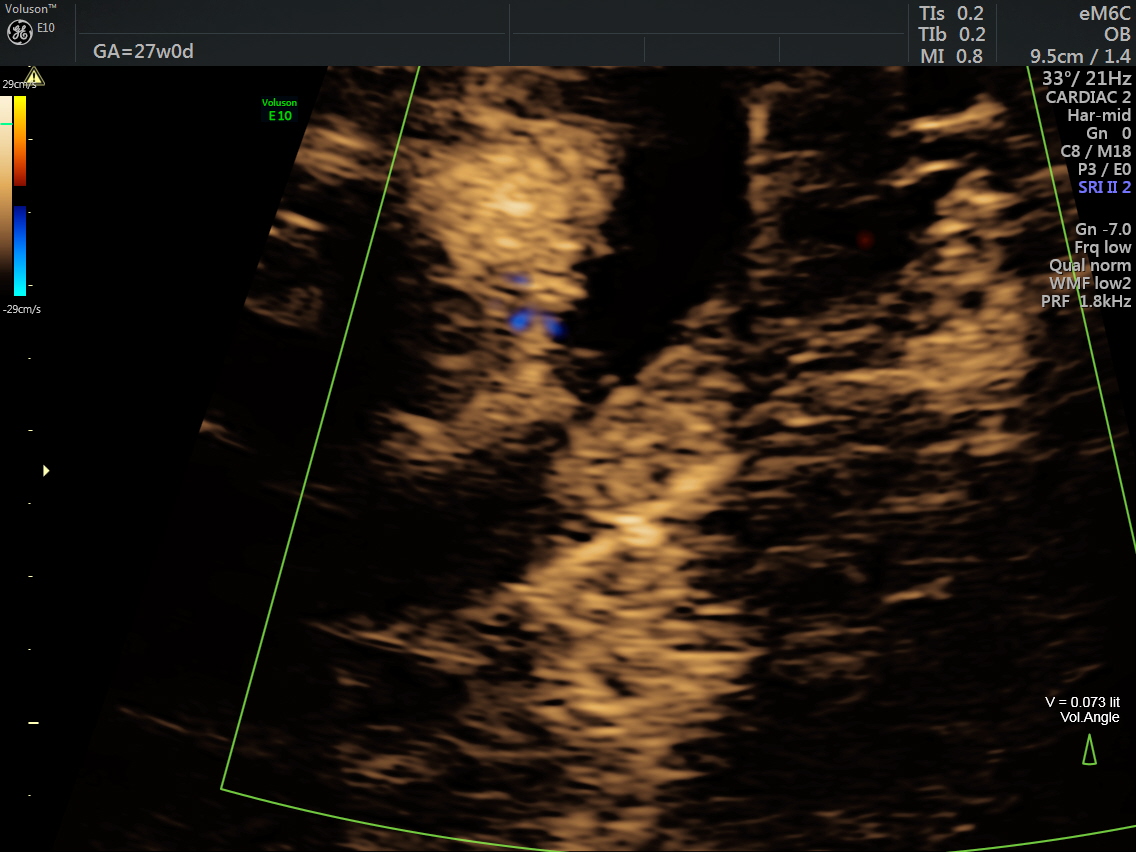

RT AORTIC ARCH_18 Published June 17, 2016 at 1136 × 852 in Rt aortic arch and aberrant left subclavian artery ← Previous Next →